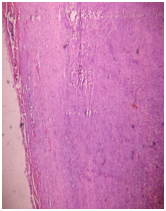

Intra operatively there were wide BP fluctuations (from 50 to 210 mm Hg Systolic). Direct vascular connections from right common iliac artery and venous tributaries to IVC were ligated. Tumor was removed en-bloc. Post operatively maintained the blood pressure with tapering of alpha blockers. Patient had an uneventful post-operative recovery. The histopathology of the specimen confirmed the diagnosis of Paraganglioma (Figure 1-7).

Figure 6 Histopatholgy showing well encapsulated tumor.